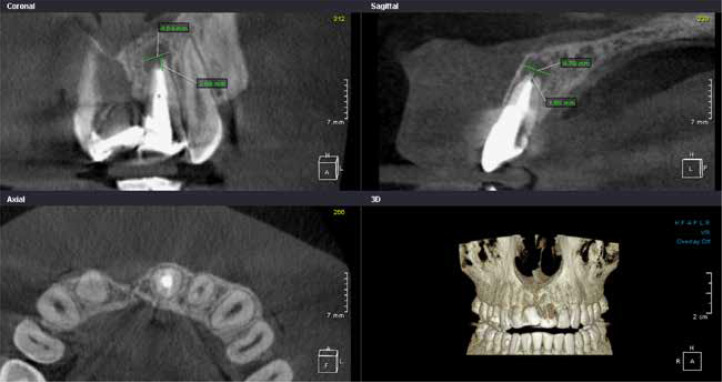

Purpose: The purpose of this study was a retrospective cross-sectional study of the Polish subpopulation, performed to evaluate the quality of endodontic treatment (ET) and the condition of the periapical tissues of permanent teeth based on cone-beam computed tomography (CBCT) images.

Material and methods: The retrospective study included a group of patients who underwent CBCT at the University Dental Clinic of the Pomeranian Medical University in Szczecin. An endodontically treated tooth index (ETTI) was used to evaluate ET. Once apical periodontitis was recognised, the size, extent, and ratio of adjacent anatomical structures were assessed using the complex periapical index (COPI).

Results: Analysis of the CBCT images showed that ET was performed in 9.9% of the teeth examined, of which 52.7% of the canals were treated correctly, while 28.1% of the root canals were found to be underfilled, 6.8% were overfilled, 9.3% of the root canals were not obturated at all, and in 3.1% of the teeth examined, the filling material was only visible in the pulp chamber. Apical periodontitis was observed in 6% of all teeth examined, while the percentage of teeth following ET was 38.5%.

Conclusions: The quality of the ET provided to the Polish subpopulation is unsatisfactory. Lack of root canal filling homogeneity is a significant risk factor for ET failure. Improper ET and poor quality of crown restoration after ET have an impact on the increased risk of occurrence, size, degree of root coverage, and extent of inflammatory periapical lesions in relation to adjacent anatomical structures.